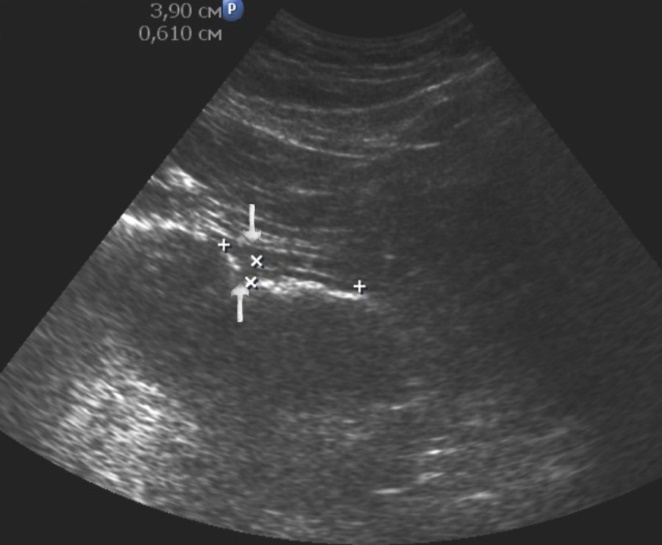

Distal gastric cancer was observed in 24 (39,3%) cases and contributed to the development of pyloric stenosis: in 6 (9,8%) cases it was compensated, in 18 (29,5%) – was sub compensated. The layers of the wall were not differentiated in all patients with sub compensated pyloric stenosis. In the case of compensated pyloric stenosis, the thickness of the affected area was 10,2±2,9mm, the length was 27,1±6,2mm, the diameter of the pylorus was 8,3±0,8mm (Figure 14). Among patients with sub compensated pyloric stenosis, the thickness of the stomach wall was 19,8±4,1mm, the length was 43,6±4,5mm, the pyloric diameter was 4,3±1,1mm (Figure 15).

Figure 14.Gastric carcinomas of diffuse infiltrative form in the atrium of T2 stage. Compensated pyloric stenos. On an empty stomach in the cavity of the stomach is determined an a small amount of fluid. The diameter of the pyloric canal more than 7 mm.

Figure 15.Distal gastric carcinomas of diffuse infiltrative form of T3 stage. Sub compensated pyloric stenos (arrows). The thickness of the anterior wall of the stomach is 9,13 mm, extent of the affected area – 7,84 cm. On an empty stomach in the cavity of the stomach is determined an a large amount of fluid. The diameter of the pyloric canal is about 6 mm.